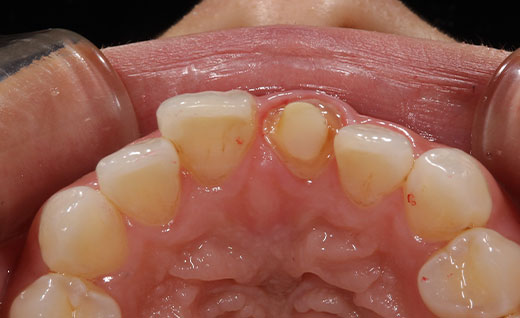

施術後

術後です。ホワイトニングをしたので術前に比べ歯は白く明るくなりました。また前歯の虫歯の治療もできるだけ目立たないように心がけ治療を行っております。術前では黒ずみや虫歯後がくっきり見えるのに対して術後ではほとんどわからず自然な見た目となります。